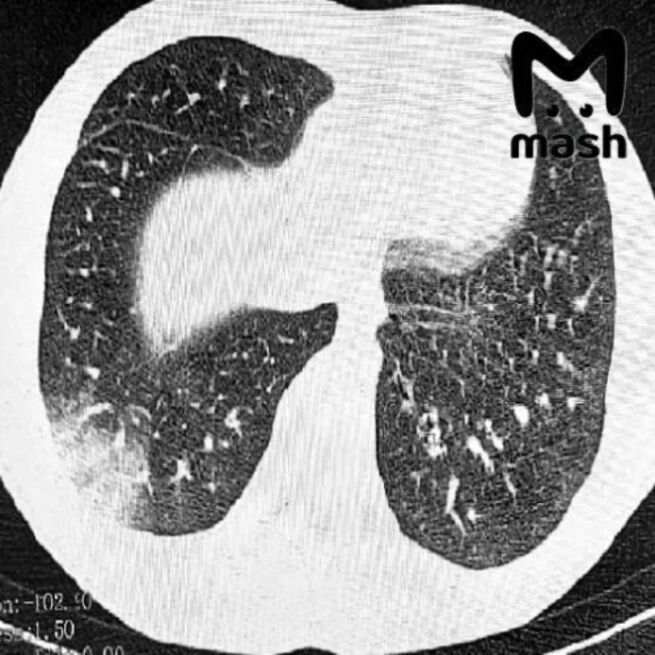

16‑летний подросток почти утратил способность дышать самостоятельно – ему понадобилась искусственная вентиляция лёгких. У другого пациента диагностировали двустороннее поражение лёгочных тканей, известное как "попкорновая болезнь". Юношу срочно прооперировали, врачи смогли спасти его жизнь.

Фото: телеграм-канал «Mash»